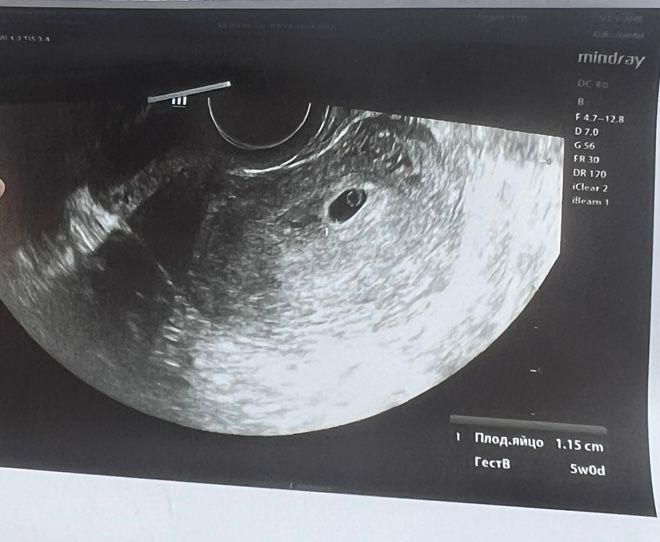

30.06 было первое узи, ПЯ 1,15 см, эмбриона не видно было, желточный мешок был.